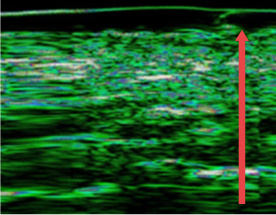

04. 피부 진피층 두께 변화

노화, 잦은 시술, 외부 자극으로 인해 얇아진 피부의 진피층을 개선합니다.

• radiesse_img11

시술 전

• radiesse_img12

4개월 후

(진피층 두께 12% 증가)

• radiesse_img13

7개월 후

(진피층 두께 27% 증가)